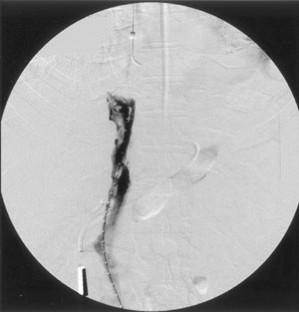

Percutaneous Stent Placement as Treatment of Renal Vein Obstruction Due to Inferior Vena Caval Thrombosis

A patient who had undergone his third orthotopic liver transplantation nearly 9 years prior to presentation developed worsening hepatic and renal function, as well as severe bilateral lower extremity edema. Magnetic resonance imaging demonstrated vena caval thrombosis from the suprahepatic venous anastomosis to the infrarenal inferior vena cava, obstructing the renal veins. This was treated by percutaneous placement of metallic stents from the renal veins to the right atrium. At 16 months clinical follow-up, the patient continues to do well.

Figure 3